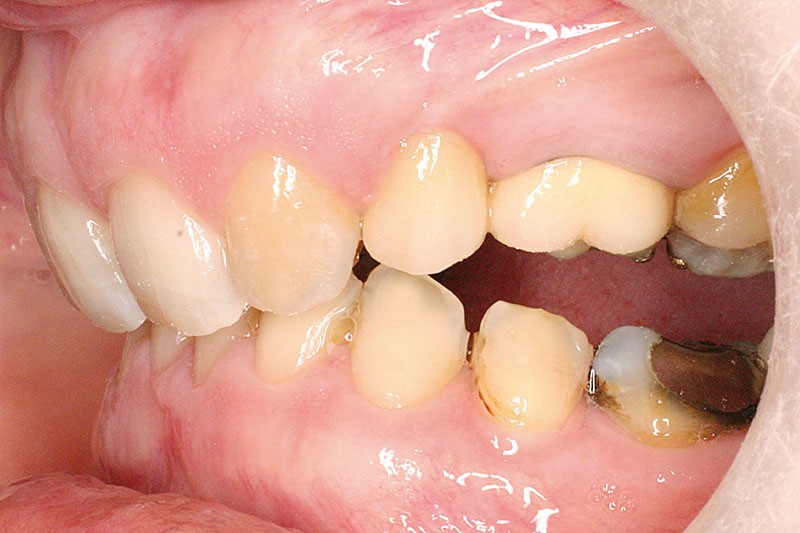

Malocclusion de classe II par rétrognathie mandibulaire dans un schéma squelettique hypodivergent (fig. 4 à 6).

On note une forte supraclusion incisive (fig. 7 à 9).